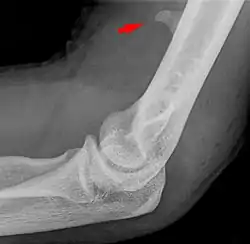

![]() Larger supracondylar process seen on a lateral radiograph of the elbow | |